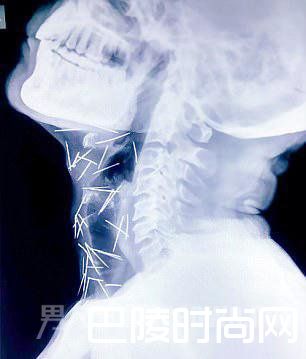

体内被插75根针,还不知道被谁扎得,这种稀奇事你听过吗?近日,印度的一位56岁男子在医院检查中发现,自己的喉部和脚踝居然有大大小小75根银针,X光片看的都非常的吓人。

近日,印度北部拉贾斯坦邦科塔市的56岁男子米纳(Badrilal Meena)到医院为脚趾进行常规手术,但医生在他的X光检查中发现他的脚、手臂和喉咙中发现75根针,米纳表示不知道原因,医生诊断为针明显是被故意插入体内的。

喉部的银针

米纳在当地的一家铁路公司工作,他的家人也对事件毫不知情,迄今为止,他们问诊的所有医院中没有一间愿意做手术把针取出,75根针中有40支根于喉咙、25根在右腿、2根在手臂。米纳被迫只能在孟买的病床上等待。